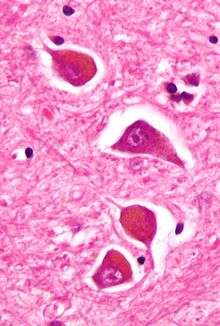

| Micrograph of Alzheimer type II astrocytes, as may be seen in hepatic encephalopathy. | |

There are various explanations why liver dysfunction or portosystemic shunting might lead to encephalopathy. In healthy subjects, nitrogen-containing compounds from the intestine, generated by gut bacteria from food, are transported by the portal vein to the liver, where 80–90% are metabolised through the urea cycle and/or excreted immediately. This process is impaired in all subtypes of hepatic encephalopathy, either because the hepatocytes (liver cells) are incapable of metabolising the waste products or because portal venous blood bypasses the liver through collateral circulation or a medically constructed shunt. Nitrogenous waste products accumulate in the systemic circulation (hence the older term "portosystemic encephalopathy"). The most important waste product is ammonia (NH3). This small molecule crosses the blood–brain barrier and is absorbed and metabolised by the astrocytes, a population of cells in the brain that constitutes 30% of the cerebral cortex. Astrocytes use ammonia when synthesising glutamine from glutamate. The increased levels of glutamine lead to an increase in osmotic pressure in the astrocytes, which become swollen. There is increased activity of the inhibitory γ-aminobutyric acid (GABA) system, and the energy supply to other brain cells is decreased. This can be thought of as an example of brain oedema of the "cytotoxic" type.[7]